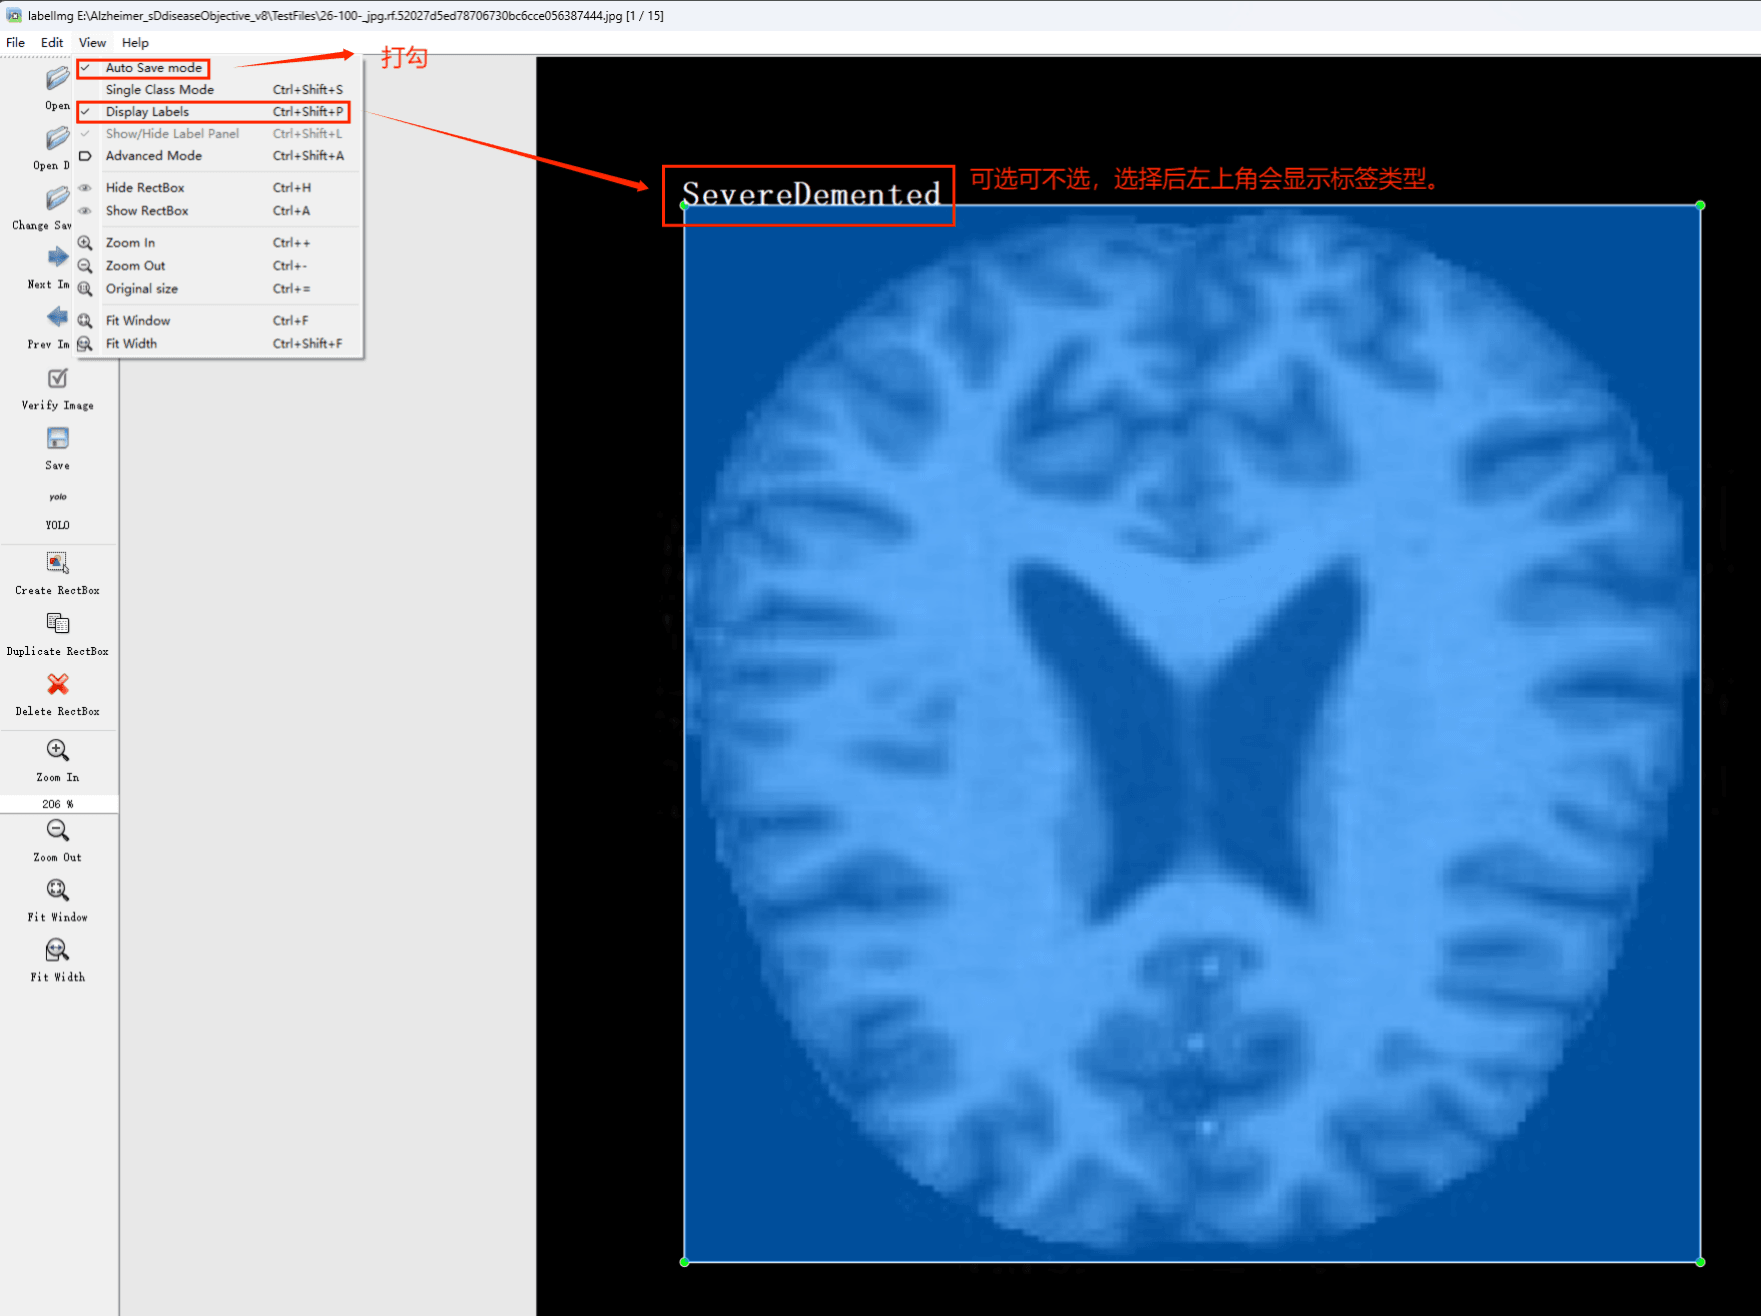

通过搜集关于数据集为各种各样的阿尔兹海默症相关图像,并使用Labelimg标注工具对每张图片进行标注,分4个检测类别,分别是”SevereDemented”,”VeryMildDemented”,”MildDemented”,”NonDemented”,”ModerateDemented”。

目标检测标注工具

(1)labelimg:开源的图像标注工具,标签可用于分类和目标检测,它是用python写的,并使用Qt作为其图形界面,简单好用(虽然是英文版的)。其注释以 PASCAL VOC格式保存为XML文件,这是ImageNet使用的格式。此外,它还支持 COCO数据集格式。

初识labelimg

打开后,我们自己设置一下

在View中勾选Auto Save mode

接下来我们打开需要标注的图片文件夹

并设置标注文件保存的目录(上图中的Change Save Dir)

接下来就开始标注,画框,标记目标的label,然后d切换到下一张继续标注,不断重复重复。